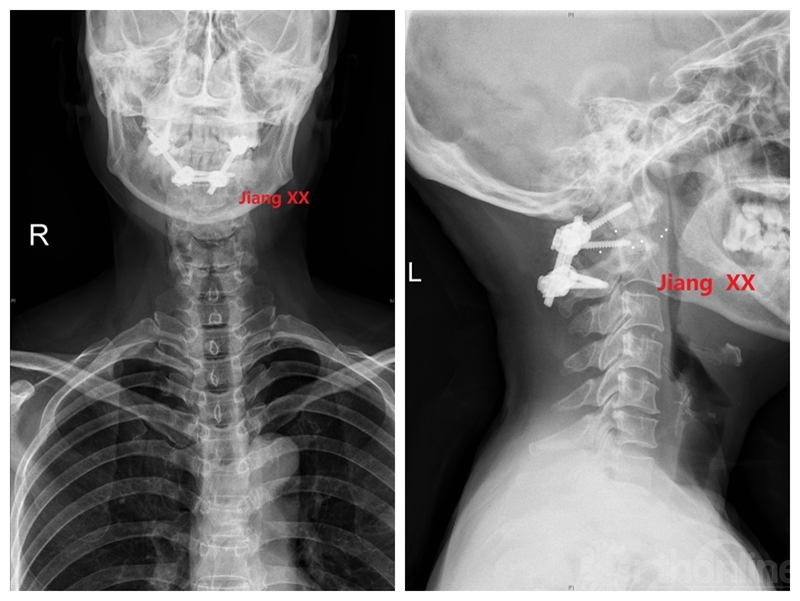

术后X线

术后一年CT